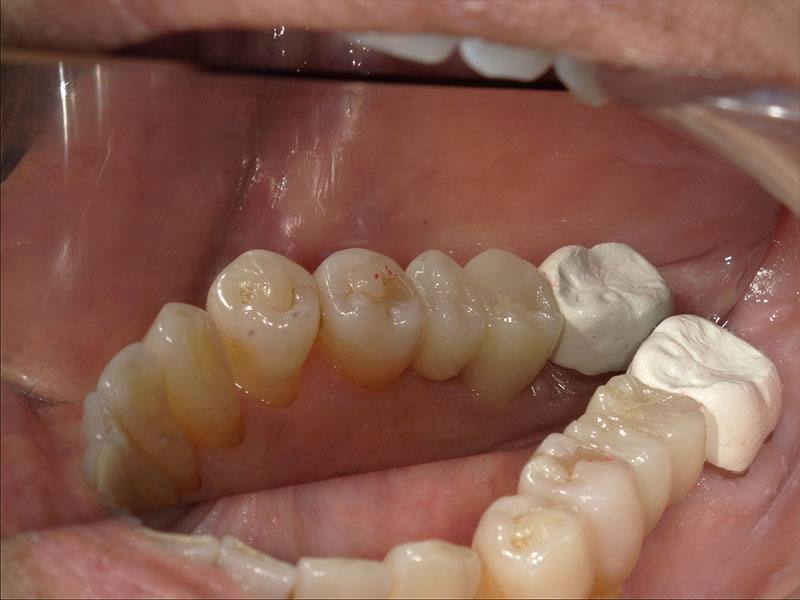

インプラント埋入手術

インプラントの埋入に関しては1回法で行いました。抜歯した部位の骨はしっかりと治癒していました。インプラント埋入後はヒーリングキャップを装着しました。手術時は特に大きな問題はなく無事に手術が終了しました。インプラントの露出を避けるためにも骨幅が少しでも広いところに埋入するために理想的な位置よりは少し後ろになっています。

インプラント部印象

インプラント埋入後におよそ3ヶ月後にインプラント部の型取りを行いました。クローズドトレー法で行いました。